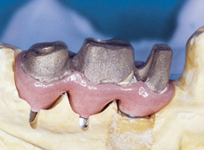

Pevné můstky – lepené nebo šroubované

S pomocí zubních implantátů můžeme díky různým kotevním systémům (třmeny, kulové hlavy, Locatory) zajistit stabilitu a držení protézy nebo při použití většího počtu implantátů zhotovit pevné náhrady – můstky nalepené nebo našroubované na pevno na implantáty.

S těmito typy náhrad můžeme dosáhnout perfektní funkci, výbornou estetiku, fonetiku a současně zajistit u pacienta možnost dobré hygienickou péče a čištění, která je pro životnost implantátů velice důležitá.